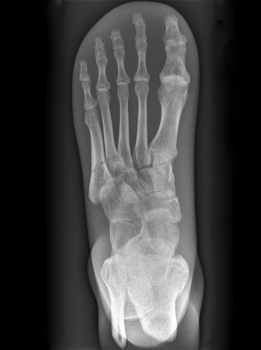

Dieses Röntgen-Teilphantom bietet Ihnen die einmalige Möglichkeit, reale Röntgenaufnahmen so oft Sie wollen zu wiederholen. Das Modell enthält echte menschliche Knochen und erlaubt so, echte Aufnahmen zu machen. Das Modell eignet sich perfekt für Schulen und Ausbildungsstätten, aber natürlich auch für die Medizintechnik, da verschiedene Einstellungen mit dem gleichen Körperteil wieder und wieder ausprobiert werden kann, ohne dass eine Gefährdung des Patienten in Kauf genommen werden muss. Das Modell ist in transparentem Kunststoff fest eingebettet. Diese Ausführung ist mit einem undurchsichtigen Lack versehen, so dass die inneren Strukturen nicht zu erkennen sind. Bei diesem Modell handelt es sich um ein handgefertigtes Einzelstück, das in seiner Größe und Ausführung abweichen kann. Bedingt durch das Fertigungsverfahren können im Innern des Phantoms Verfärbungen oder Risse vorhanden sein, dies ist produktionsbedingt und stellt keinen Defekt dar. Der Verkauf dieses Modells erfolgt nur gegen Nachweis der medizinischen Verwendung.

Fußskelett mit Unterschenkelansatz.